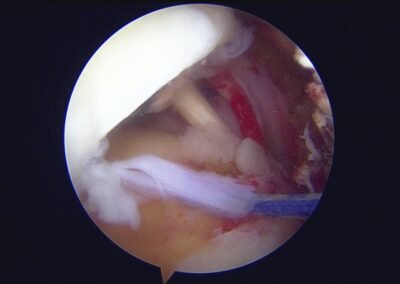

GalleryShoulder rotator cuff repair Meniscus root repair Meniscus repair Bankart repair for recurrent shoulder dislocation ACL reconstruction Machines Instruments